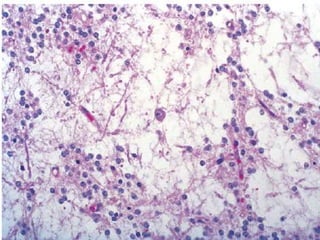

Dysplastic Neurons

Dysplastic neurons embedded in a dense

Histopathology:

•Neuronal + glial cell elements.

•Dysplastic neurons are characterized by

(i) loss of cytoarchitectural organization

(ii) abnormal (subcortical) localization

(iii) clustered appearance

(iv) cytomegaly

(v) perimembranous aggregated Nissl

substance

(vi) presence of bi- or multinucleated

neurons.